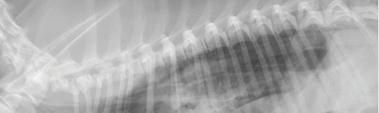

Se realizaron radiografías torácicas y en la proyección lateral derecha se observó, craneal a la silueta cardiaca, una opacidad tejido blando mal definida que producía efecto silueta positivo con esta. La tráquea se visualizó desplazada dorsalmente y el atrio izquierdo aumentado de tamaño. El parénquima pulmonar mostraba un aumento de opacidad en su área caudodorsal, compatible con un patrón pulmonar intersticial no estructurado difuso, el cual se consideró normal debido a que la radiografía fue tomada en fase espiratoria inicial

163

y a la condición corporal del paciente. En la proyección ventrodorsal, el mediastino craneal se observó en el límite superior de tamaño, presentándose un tamaño dos veces superior a la anchura de la vértebra torácica (Fig. 1). Este cambio es compatible con una imagen artefactual secundaria a la leve rotación que presenta la radiografía y a la condición corporal del paciente. El diagnóstico radiológico más probable fue una masa mediastínica craneoventral y cardiomegalia izquierda. En la ecocardiografía transtorácica se confirmó el diagnóstico de enfermedad degenerativa de la válvula

Figura 1. Radiografías torácicas en proyección lateral derecha (A) y ventrodorsal (B) donde se visualiza el área de opacidad de tejido blando craneal a la silueta cardíaca (flechas blancas). En la proyección ventrodorsal se visualiza el mediastino craneal que se presenta en el límite superior de grosor (flechas rojas).